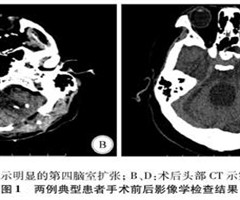

颅内感染后孤立性第四脑室4例并文献复习

【摘要】目的探讨颅内感染后孤立性第四脑室的诊断和治疗。方法回顾性分析航空总医院神经外七科2018年2月—2020年1月收治的4例孤立性第四脑室患者的临床资料,并对相关文献进行复习。结果4例孤立四脑室病例均继发于颅内感染后,均已行侧脑室外引流...